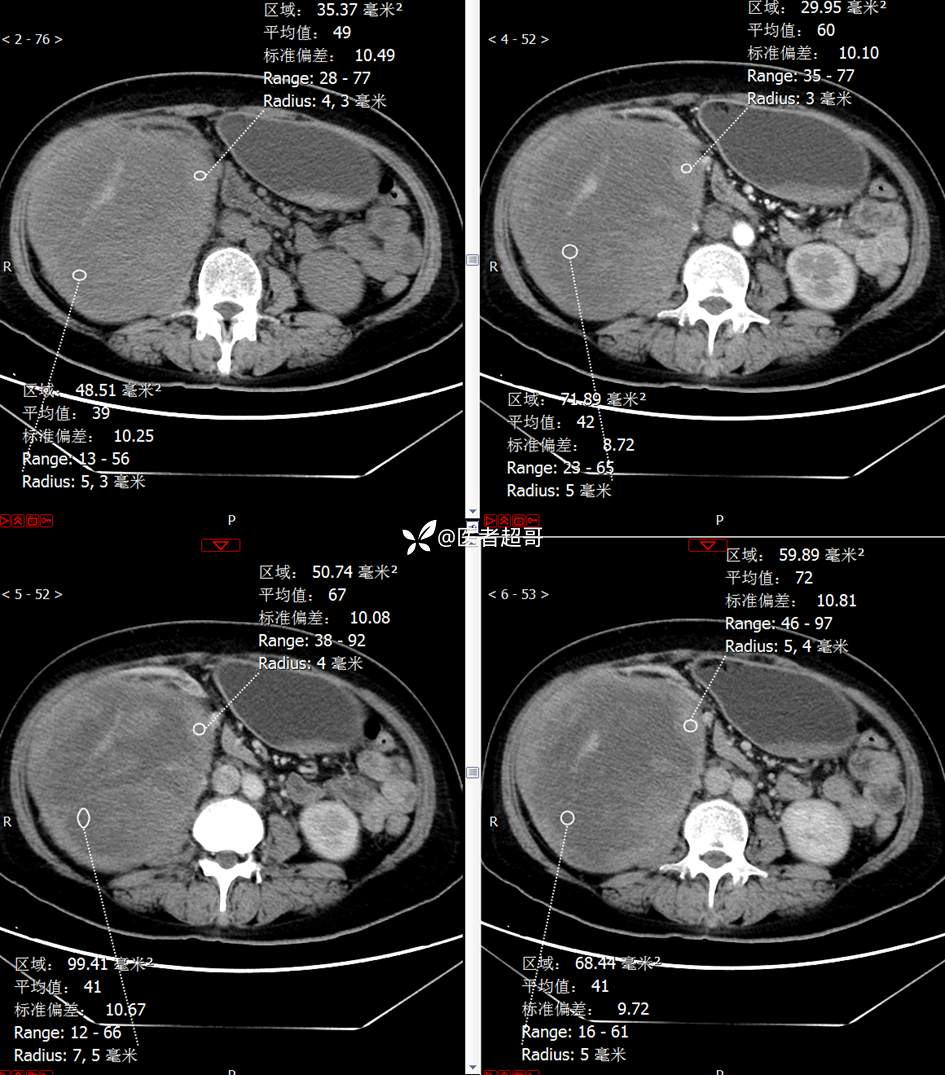

现病史:患者1周余前发现右上腹有一半球形巨大肿物,约18cm*15cm大小,既往贫血病史3年余,诉乏力,易疲劳,偶有头晕,活动后心悸,无腹痛、腹胀,无恶心、呕吐,无尿频、尿急、尿痛,无排尿困难,患者为求进一步治疗,来我院消化内科就诊,门诊行肝.胆.胰.脾.肾彩超示:右肾上部囊实性占位,范围约18.0cm×11.7cm×16.4cm,边界清,形态规则,建议进一步检查,腹膜后实性结节。我科遂以“肾肿物”收治入院,患者自发病以来,神志清、精神可,睡眠、饮食可,二便正常,体重、体力略有下降。